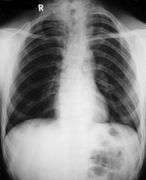

Different features of the dysostosis are significant. Radiological imaging helps confirm the diagnosis. During gestation (pregnancy), clavicular size can be calculated using available nomograms. Wormian bones can sometimes be observed in the skull.[16]

|